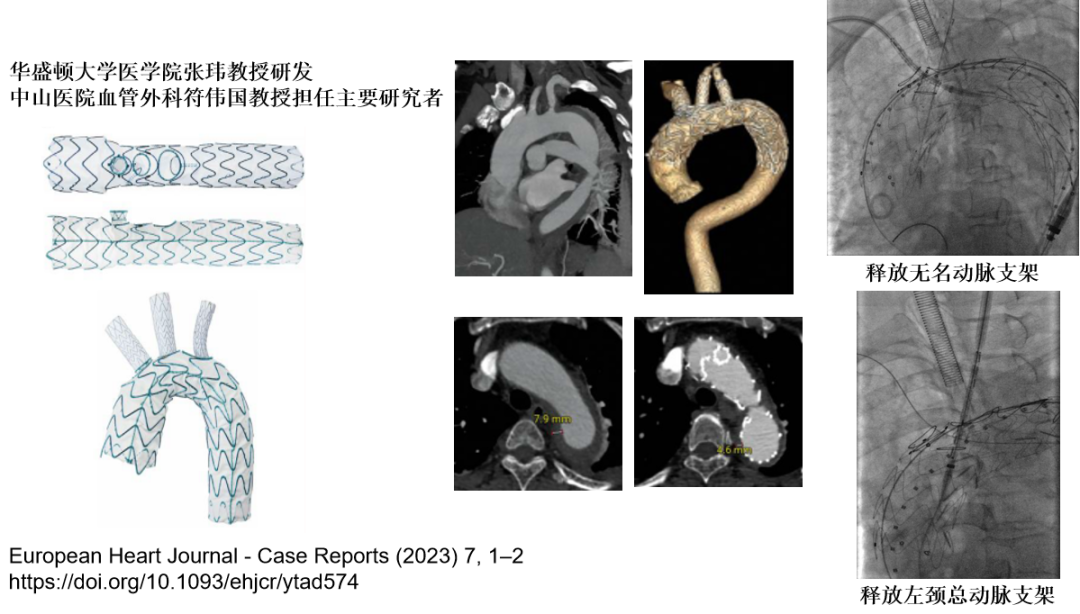

ZIPPER™⼀体式主动脉弓覆膜支架系统

腔内解决现状 — 三分支支架

优势:采用独特的“自适应分支支架”+“槽式主体支架设计”,满足弓部三个分支的各种解剖差异性,彻底解决困扰该疾病的重大痛点,在全球首次实现弓部及分支支架均经导管介入植入及解剖型矫治。

特点:

弓部三分支解剖性重建

所有支架均经股动脉导入

颈部无需切口,颈部三分支动脉无需搭桥

采用独特的自适应特性

弓部三分支解剖性重建:分支完全按照原主动脉及分支动脉解剖结构走行矫治